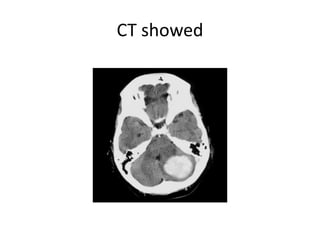

CASE 2

• 60/M

• C/O sudden onset

vertigo.

• Associated symptoms

of

– Left hemiparesis

– Imbalance on walking

• O/E

– (L) hemiparesis- UL- 4/5,

LL- 3/5

– (L) facial palsy

– (L) plantar extensor

MRI showed